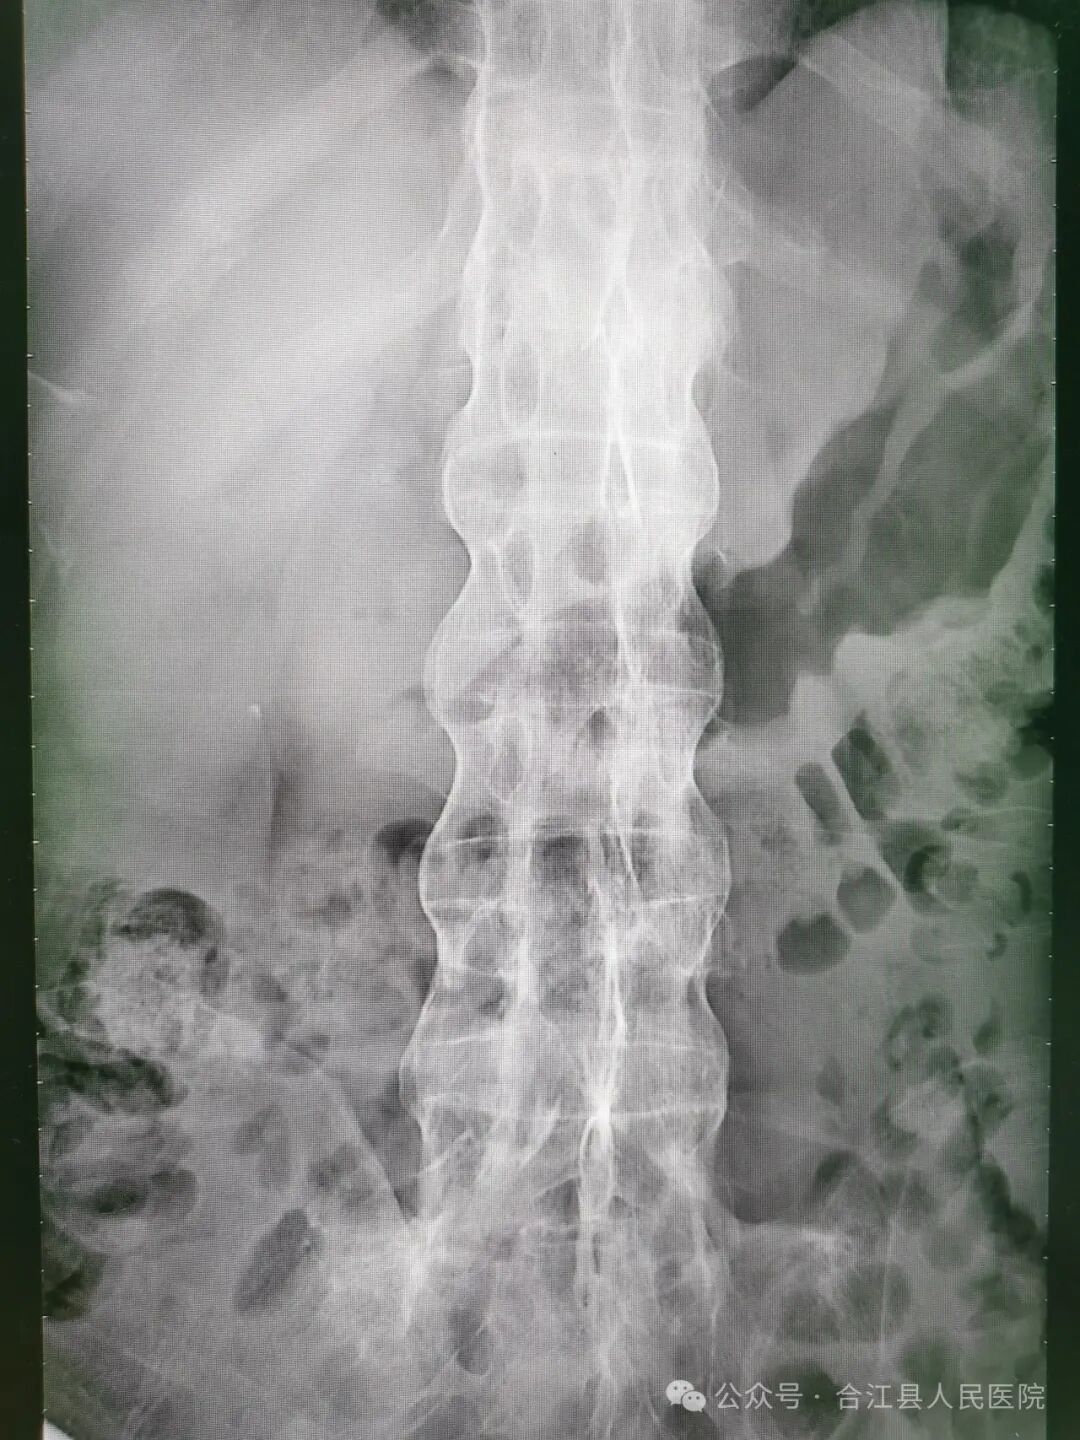

经创伤外科和麻醉科详细病史采集和查体,徐先生确实不是普通气道,气道处理非常棘手。颈椎、腰椎曲度变直,椎体“竹节样改变”。